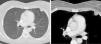

Benign metastasizing leiomyomatosis of the lung